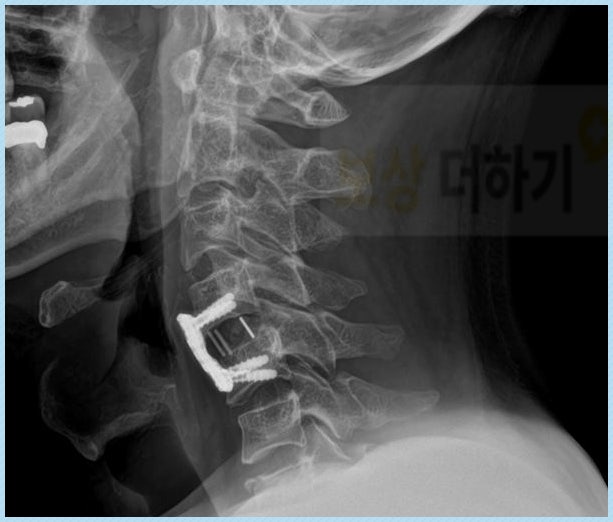

상병코드: S1220 경추 2번, 4번, 5번, 7번이 모두 골절이 되었다는 진단을 받게 되었습니다. 이에 따라 경추 4번, 5번(C4, C5)은 유합술을 받으셨어요. 이렇게 경추를 핀으로 고정시켰기 때문에 목의 움직임이 제한될 수 밖에 없죠. 이러한 경우 위에서 살펴본 것처럼 운동장해로 후유장해 평가를 받을 수 있어요. 하지만 각도의 변형 또한 동반되었기 때문에 기형장해로도 평가를 받을 수 있었죠.